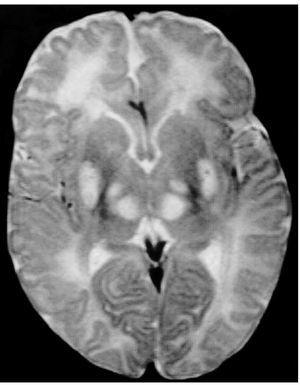

Exploraciones complementarias: hemograma normal; velocidad de sedimentación globular (VSG), 14 mm; bioquímica con normalidad de glucosa, calcio e iones; bilirrubina total, 5,2 mg/dl; bilirrubina directa, 1,1 mg/dl; GOT, 100 U/l; fosfatasa alcalina, 993 U/l, lactato deshidrogenasa (LDH), 708 U/l. Equilibrio acidobásico: pH, 7,33; presión parcial de dióxido de carbono (pCO2), 57; y de oxígeno (pO2), 50; bicarbonato, 30; exceso de bases, 4. Citoquímica y cultivo de líquido cefalorraquídeo (LCR): negativos. Enolasa neuroespecífica en LCR: 32 μg/ml (aumentada). Proteína básica de mielina en LCR: 0,3 ng/ml (0-1,5 ng/ml). Perfil de aminoácidos en sangre y orina: normales. Ácido láctico, 26,1 mg/dl (3-15 mg/dl), y ácido pirúvico, 1,6 mg/dl (0,3-1 mg/dl), aumentados en sangre. Cociente lactato/piruvato, 16. Ácido acetoacetato y 3-hidroxibutirato, aumentados. Ecografía cerebral, normal. Fondo de ojo, normal. Electroencefalograma: actividad de fondo lentificada con puntas aisladas parietotemporales izquierdas. Resonancia magnética (RM) cerebral: alteraciones de intensidad de señal (aumento en T2) bilateral y simétrica en núcleos lenticulares, tálamos, núcleos rojos mesencefálicos y protuberancia así como vermis inferior, con ausencia de mielinización en sustancia blanca de circunvoluciones pre y poscentral (fig. 1). Biopsia del músculo estriado: fibras tipo 1 con disminución anular subsarcolémica de la actividad oxidativa. Al microscopio electrónico: ausencia de fibras rojas rasgadas y presencia de fibras musculares con mitocondrias de tamaño aumentado compatible con probable anomalía mitocondrial (fig. 2). Estudio de función mitocondrial en homogenado muscular: déficit de los complejos I, III y IV de la cadena respiratoria (tabla 2).

Figura 1.RM cerebral. Corte axial: aumento de intensidad en T2 bilateral y simétrica de la sustancia blanca periventricular y núcleos de la base (tálamos y lenticular).